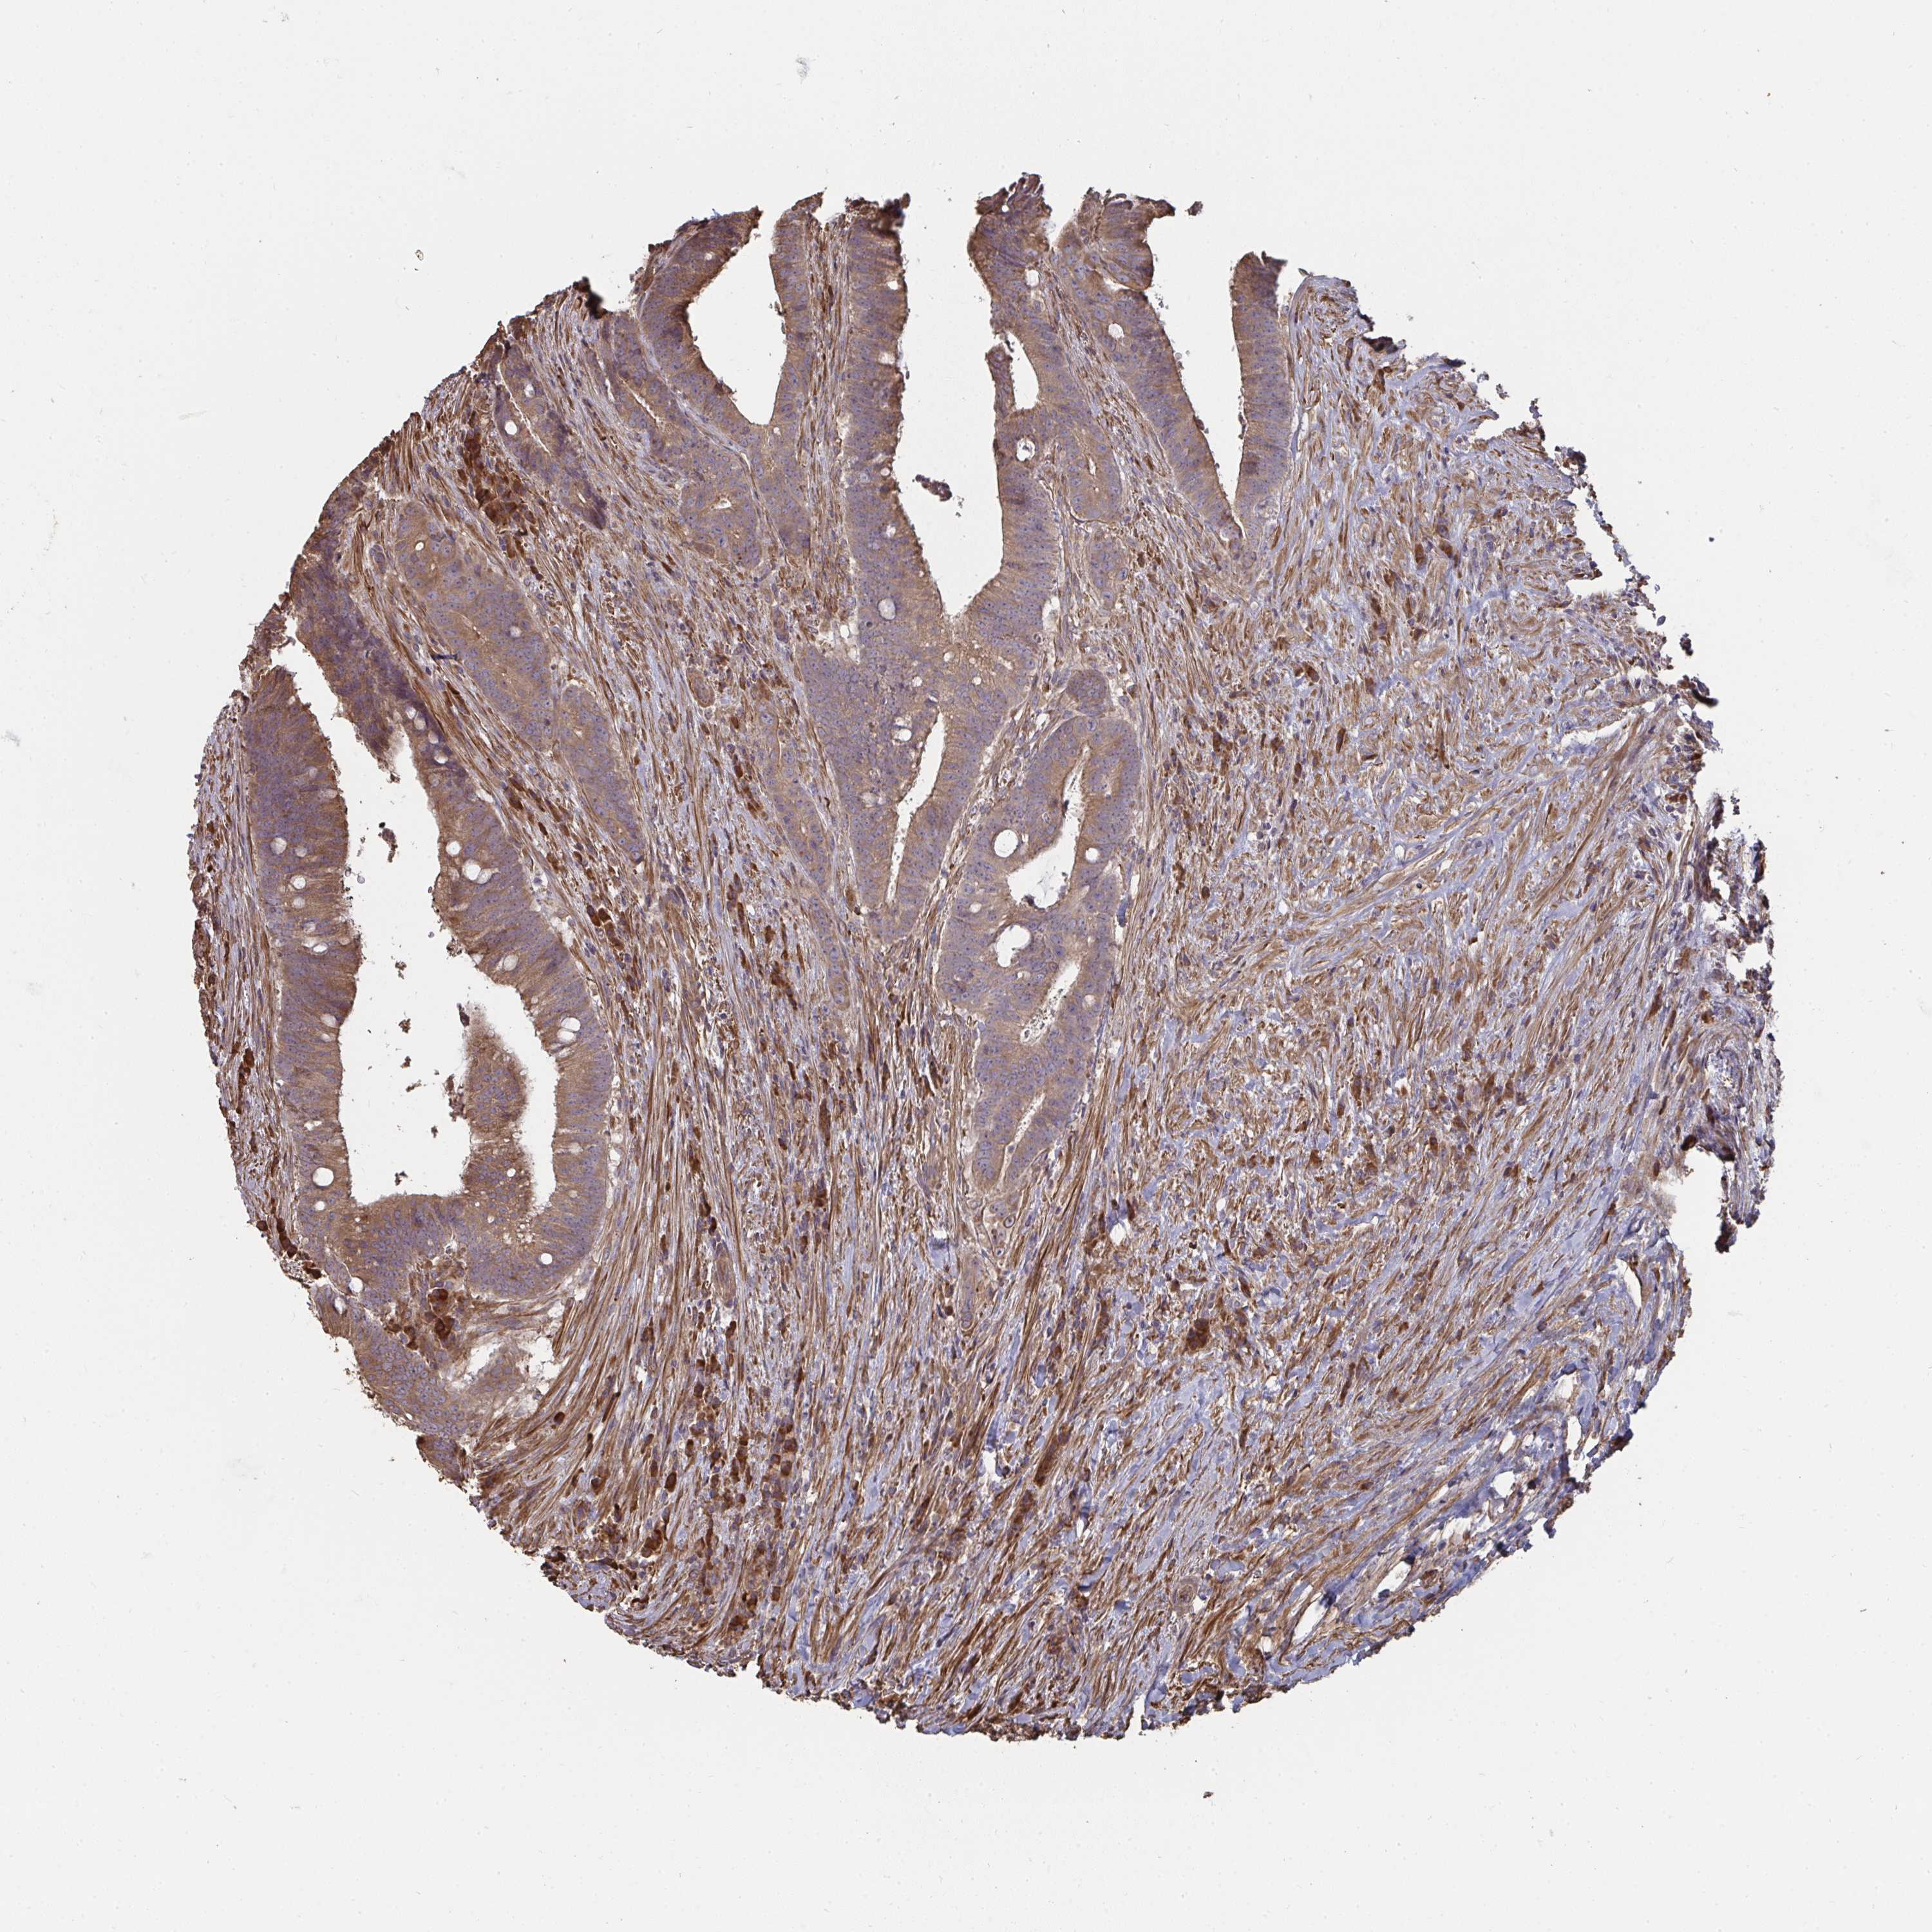

CANCER COLORECTAL CANCER Show tissue menu

ANTIBODIES

AND

VALIDATION